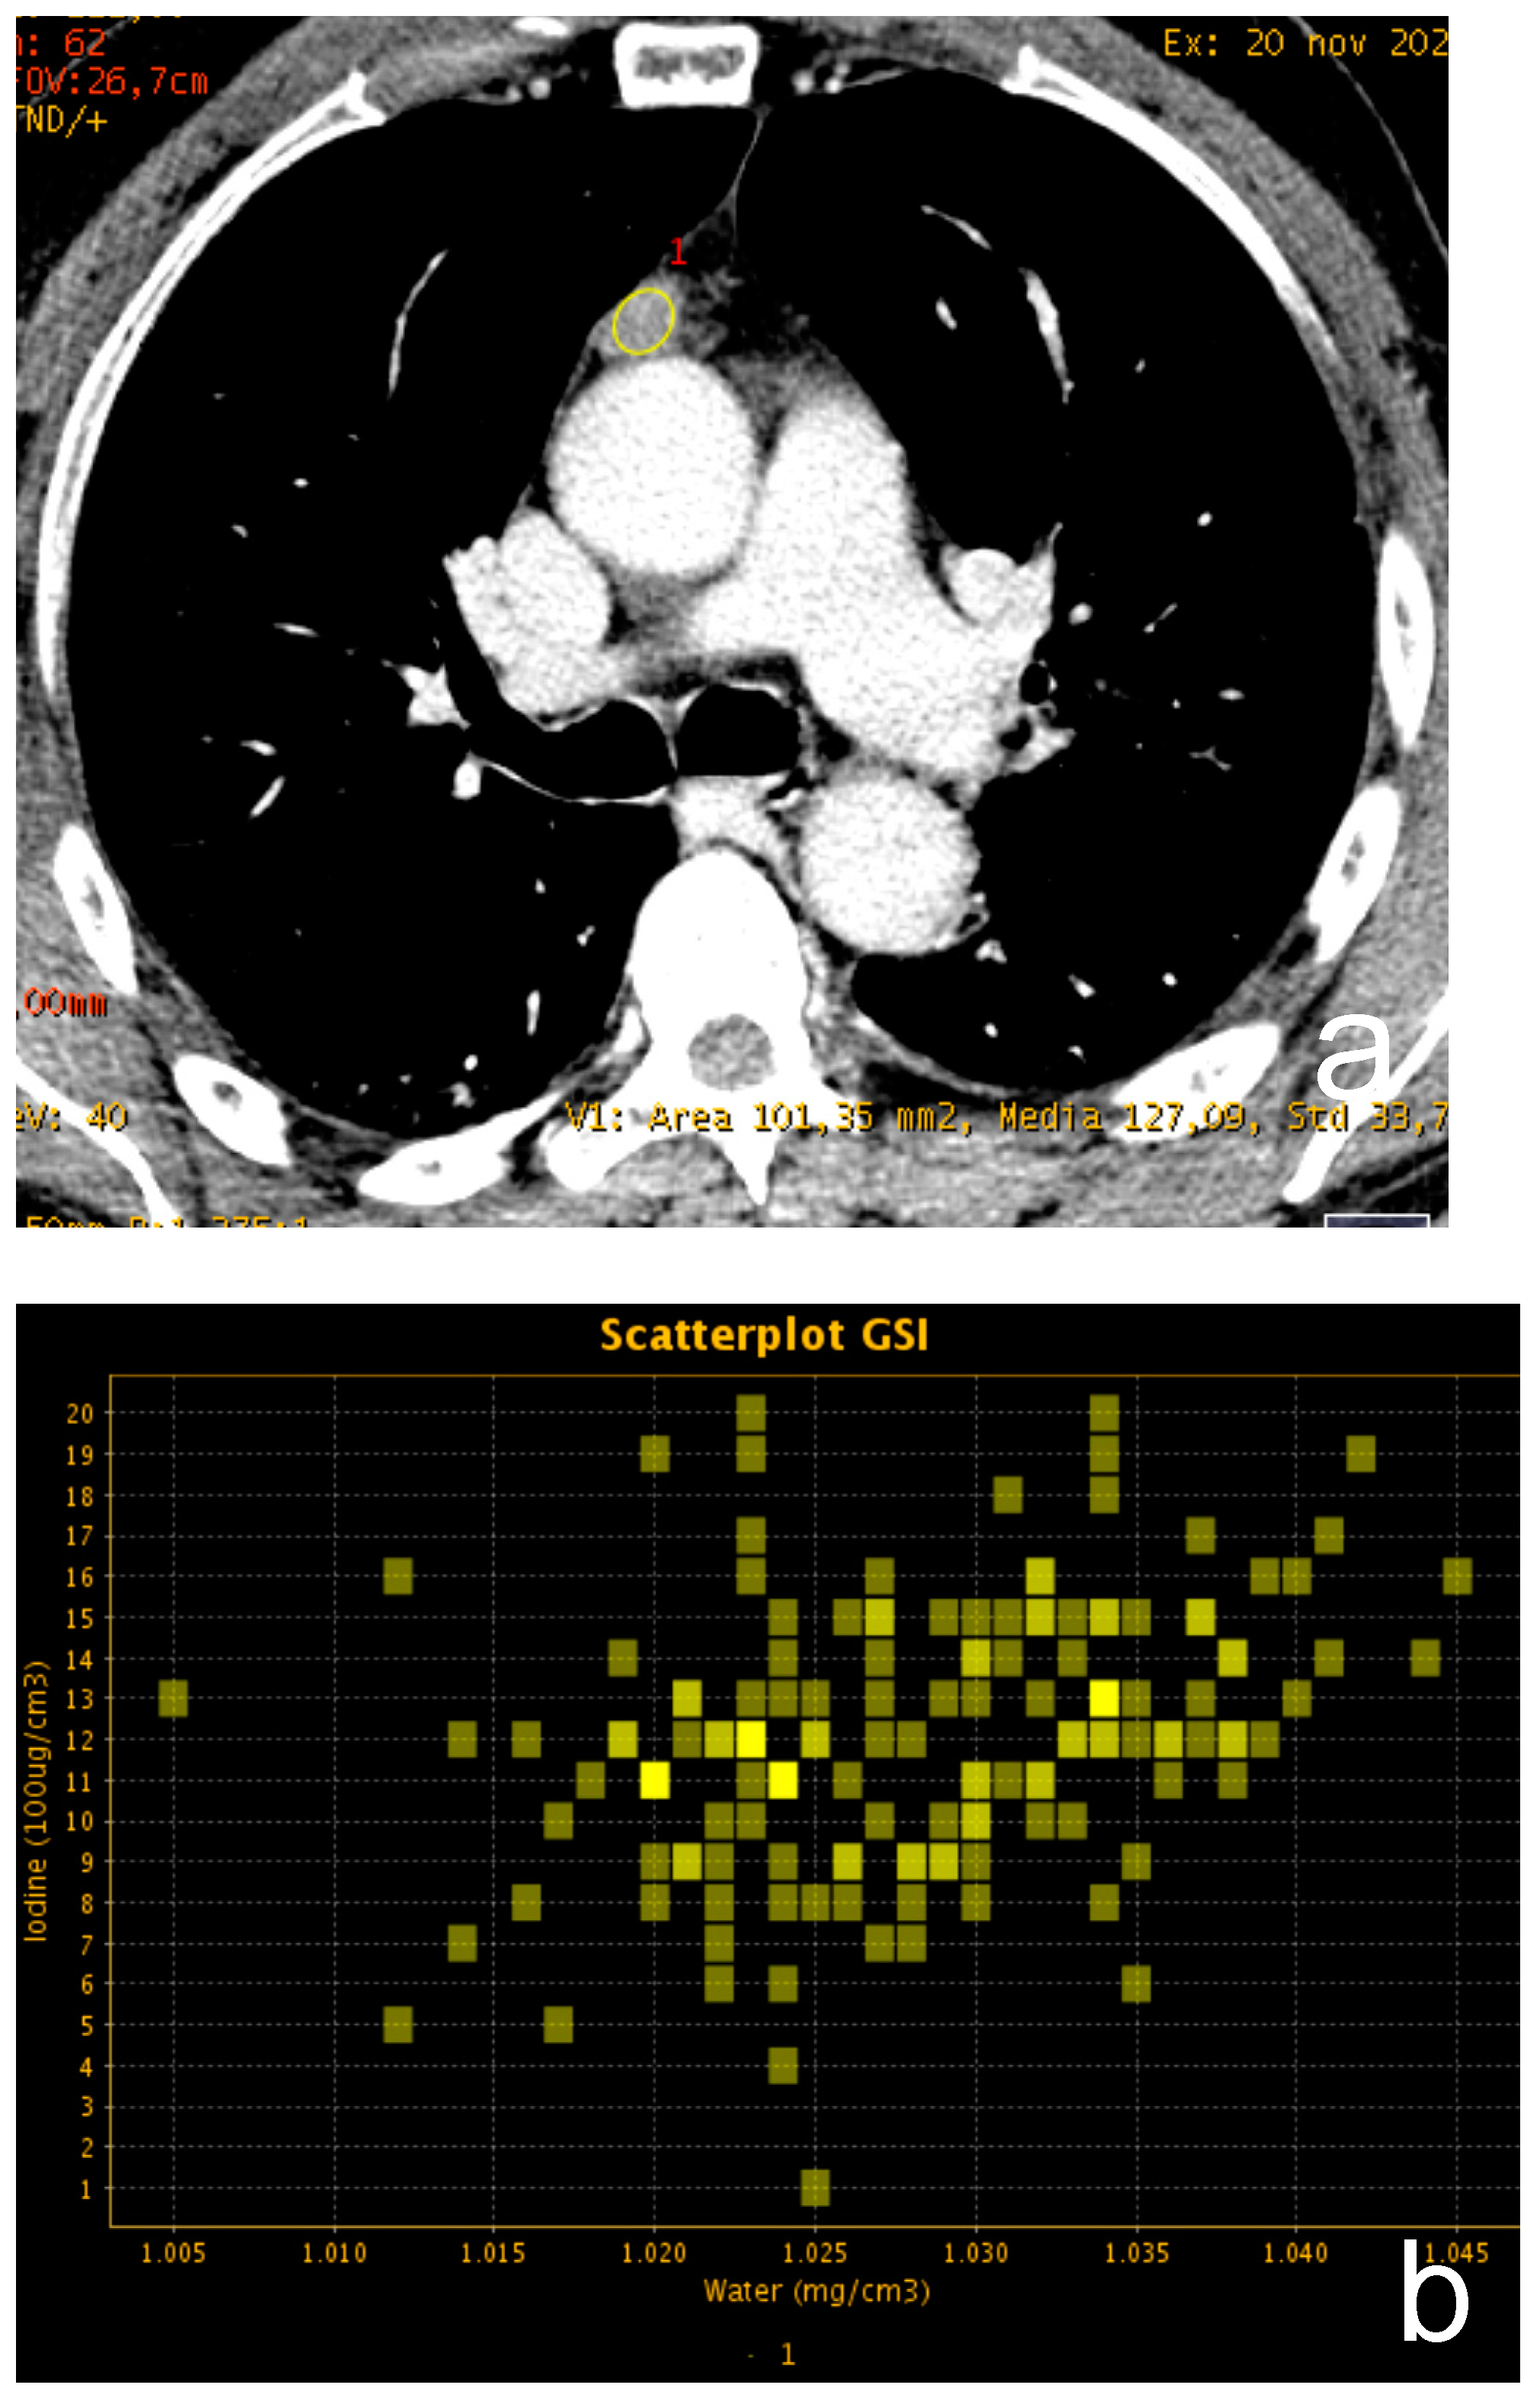

Dual-energy CT (DECT) indicates the acquisition of CT data derived from two different photon energies so that different materials can be better characterized by evaluating the difference in attenuation at these two energies [17]. Thanks to technical improvement, DECT images can be obtained with a radiation exposure not significantly different from that of a conventional single-energy CT. The scans can be performed by using different technical approaches: dual-source, single source with rapid switching, single source twin beam and dual-layer detector. Raw data can be elaborated at a dedicated workstation, thus achieving a set of monoenergetic images ranging from 40 to 140 keV and material-specific images, such as iodine and water-related. Given the increased attenuation of iodine at a low energy level, low energy series enhance lesion conspicuity with several advantages in oncologic imaging. Moreover, DECT is not affected by beam hardening artifacts, and it is possible to accurately quantify iodine uptake of tissue with better characterization of different lesions [18,19] (Figure 3).

Figure 3.

(a–c) A 62-year-old man with a small thymic lesion with convex margins. Dual-energy post-contrast images (scatterplot in (a) and spectral curve in (b) shows a mild enhancement of the lesion (mean iodine concentration 1.2 mg/dL). Histopathology revealed a medullary type A thymoma with capsule infiltration (Masaoka stage IIa).